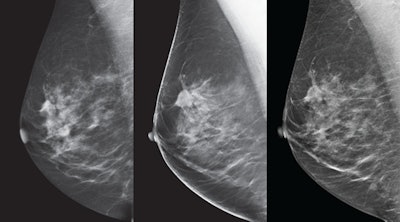

GE Healthcare's SenoClaire tomosynthesis system. All images courtesy of GE Healthcare.

Breast images from the SenoClaire tomosynthesis system. Left: 2D mediolateral oblique (MLO) view. Middle: 3D MLO view. Right: V-preview reconstructed image.And it's dose that counts, GE said: A single mediolateral oblique (MLO) view from SenoClaire is comparable to two-view digital mammography, making the exam half the dose with one compression.